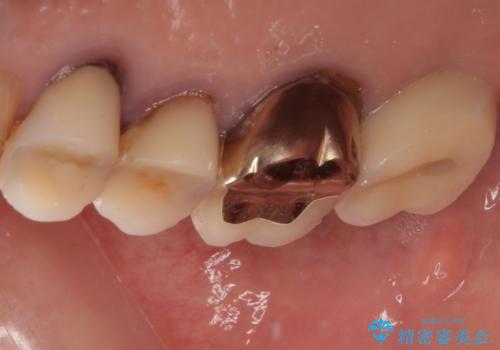

抜歯後2ヶ月でのインプラント埋入を行いましたが、骨の再生は不十分でした。

骨量は不十分でしたが、デンサーバーを用いることで無事に埋入することができ、その後は速やかに補綴治療を行うことができました。